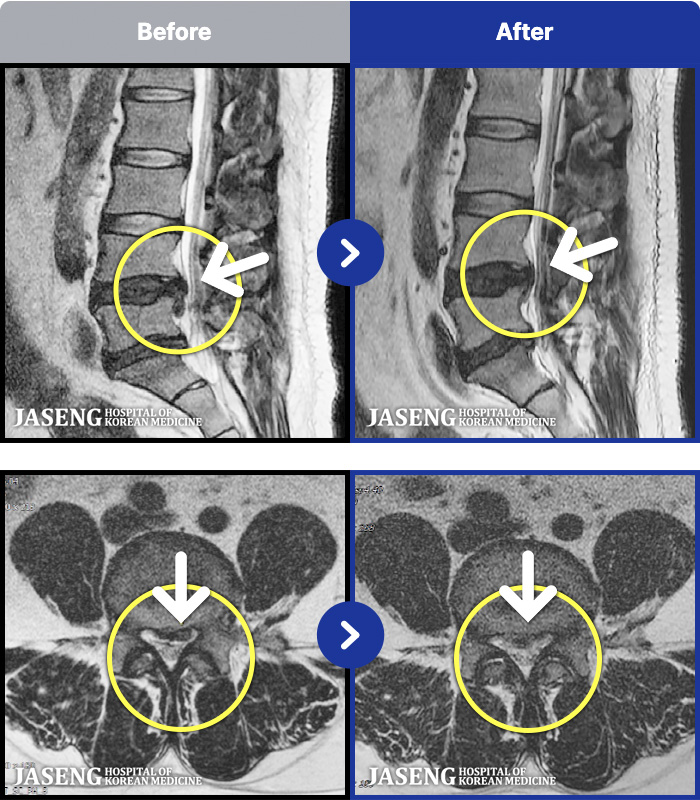

MRI ġ

1,240 MRI ũ ʸ Ȯϼ.